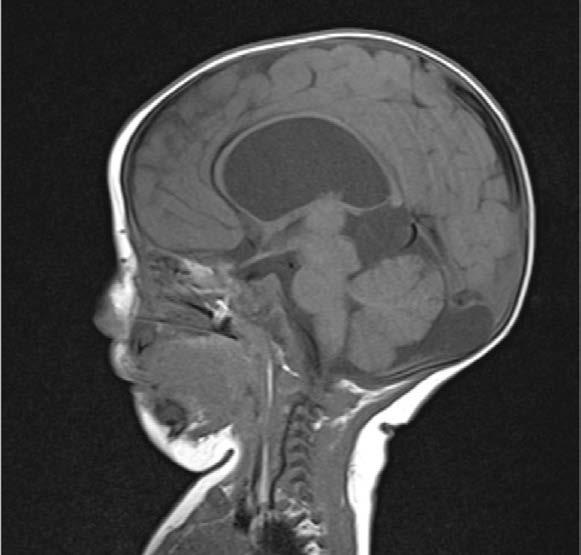

El neurólogo de la Unidad Médica de Alta Especialidad (UMAE) del Hospital de Especialidades (HE) del Centro Médico Nacional (CMN) “Adolfo Ruiz Cortines”, David Reyes Barrios, informó que el Síndrome de Moebius es un trastorno neurológico congénito poco frecuente que afec-

ta principalmente los nervios craneales VI (abducens) y VII (facial).

Además, agregó que dicho padecimiento provoca parálisis facial bilateral que impide sonreír, fruncir el ceño o cerrar los ojos completamente; así como dificultad para mover los ojos hacia los lados (estrabismo); problemas para succionar, deglutir o alimentarse, especialmente en los recién nacidos; retraso en el habla o dificultad para articular palabras; posibles malformaciones orales (micrognatia y paladar hendido) o de las extremidades (sindactilia y pie equinovaro) y problemas auditivos en algunos casos.

Del mismo modo, el neurólogo de la UMAE explicó que el diagnóstico de Moebius se realiza de manera clínica mediante la identificación de los signos y síntomas característicos; en algunos casos, se pueden uti-

lizar estudios de imagen como resonancia magnética para evaluar los nervios craneales y el tronco encefálico y pueden realizarse pruebas genéticas si se sospecha un componente hereditario.

Reyes Barrios afirmó que, este síndrome afecta a personas de todas las etnias y géneros por igual, presentándose desde el nacimiento, pues se trata de un trastorno congénito que no cuenta con una cura definitiva, pero es posible controlar los síntomas y mejorar la calidad de vida con: fisioterapia para fortalecer los músculos, terapia del habla para mejorar la comunicación cirugías reconstructivas para corregir alteraciones faciales o físicas, apoyo psicológico para afrontar el impacto social y emocional del síndrome.

El especialista recalcó que la mayoría de los casos son esporádicos, es decir, no tienen

antecedentes familiares claros, aunque en algunos casos poco frecuentes, han podido identificar un componente genético hereditario y; asimismo, invitó a las personas a sensibilizarse sobre este síndrome para fomentar un diagnóstico temprano y un manejo multidisciplinario, promoviendo así la creación de redes de apoyo puede ayudar a las familias a enfrentar los retos asociados con esta condición.